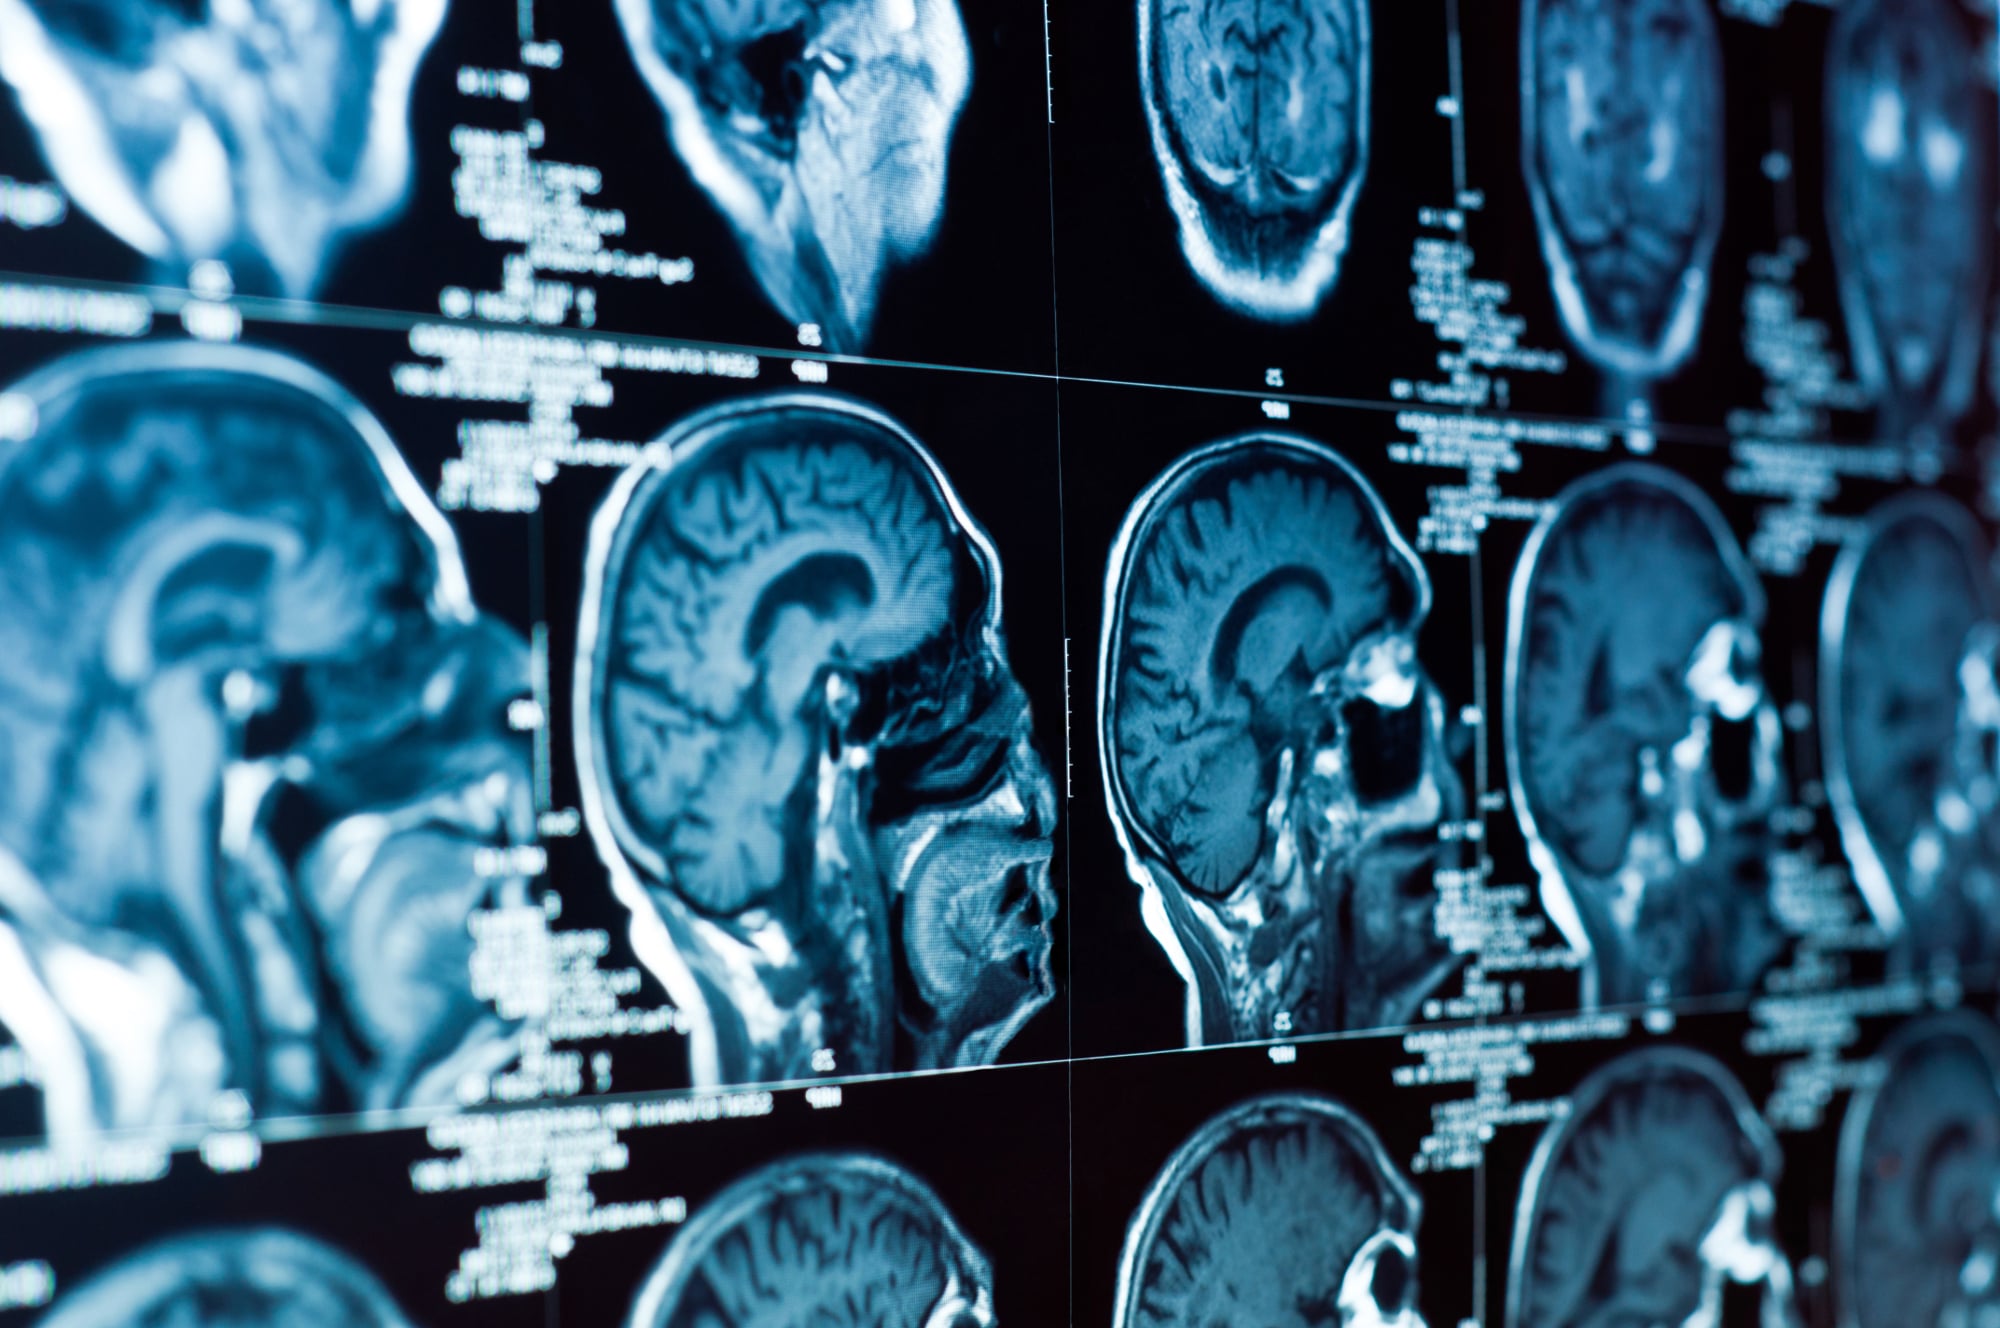

Медицинская диагностика: КТ и МРТ головного мозга